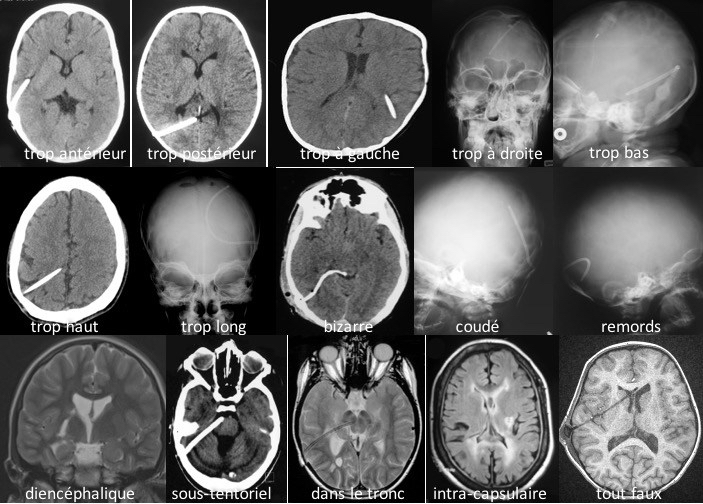

complications liées à la pose du cathéter ventriculaire